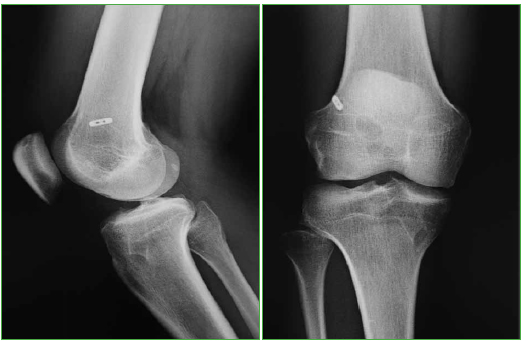

Se trata de dos series de 30 pacientes operados por el mismo cirujano utilizando injerto autólogo múltiple, de tres a cinco fascículos, de tendones autólogos homolaterales semitendinoso y recto interno, y empleando, en una de ellas, la técnica monotúnel transtibial con guía over the top para la tunelización femoral y, en la otra, la técnica bitúnel con tunelización retrógrada ciega femoral mediante FlipCutter® (Arthrex, Naples, FL, EE.UU.), fijando la plastia, en ambas técnicas, con el sistema cortical ACL TightRope® (Arthrex, Naples, FL, EE.UU.) a nivel proximal y con tornillo retrógrado interferencial (Arthrex, Naples, FL, EE.UU.) a nivel distal. La inserción tibial de la plastia se ubicó en la zona posterior de la huella anatómica, por detrás del cuerno anterior del menisco externo, para evitar la fricción intercondilar, con una inclinación sagital del túnel de 55º y la femoral en disposición posterior over the top dejando pared de 4 mm en la técnica transtibial monotúnel (Figura 1) y, en situación posterior y sobre la hora 10, en rodillas derechas y la hora 2 en las izquierdas, en la técnica anatómica bitúnel (Figura 2). La estancia hospitalaria media fue de 48 h, tiempo del mantenimiento del drenaje. Se permitió la movilidad inmediata y la marcha en carga parcial desde las 48 h. La rehabilitación posoperatoria fue similar en todos los pacientes: se inició a las tres semanas y se mantuvo un mínimo de dos meses y una media de tres.

Figura 2.

Imagen radiológica de la ligamentoplastia bitúnel anatómica.